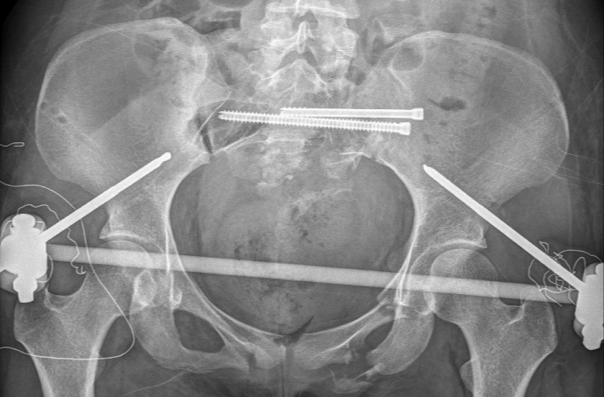

图五:术中透视验证复位结果

最后,手术团队利用智能化骨科手术机器人进行了螺钉通道及置入规划,并借助手持导向器,在实时动态三维可视化导航下,精准完成螺钉置入,完成了对该例骨盆骨折的微创治疗。

图六:螺钉置入规划、置入

术中透视验证螺钉置入效果

经过2个半小时的“数智化微创手术”,患者手术切口仅有5个,切口平均长度小于1cm,术中出血量仅有50cc,“真·微创”治疗效果着实令人满意。智能化骨科手术机器人真正实现了看得见的‘快准稳’,不仅让医生有了‘超级助手’,真正意义上实现骨盆骨折微创治疗,同时对患者康复和术后生活质量极为有利。

图七:患者术后三天影像资料